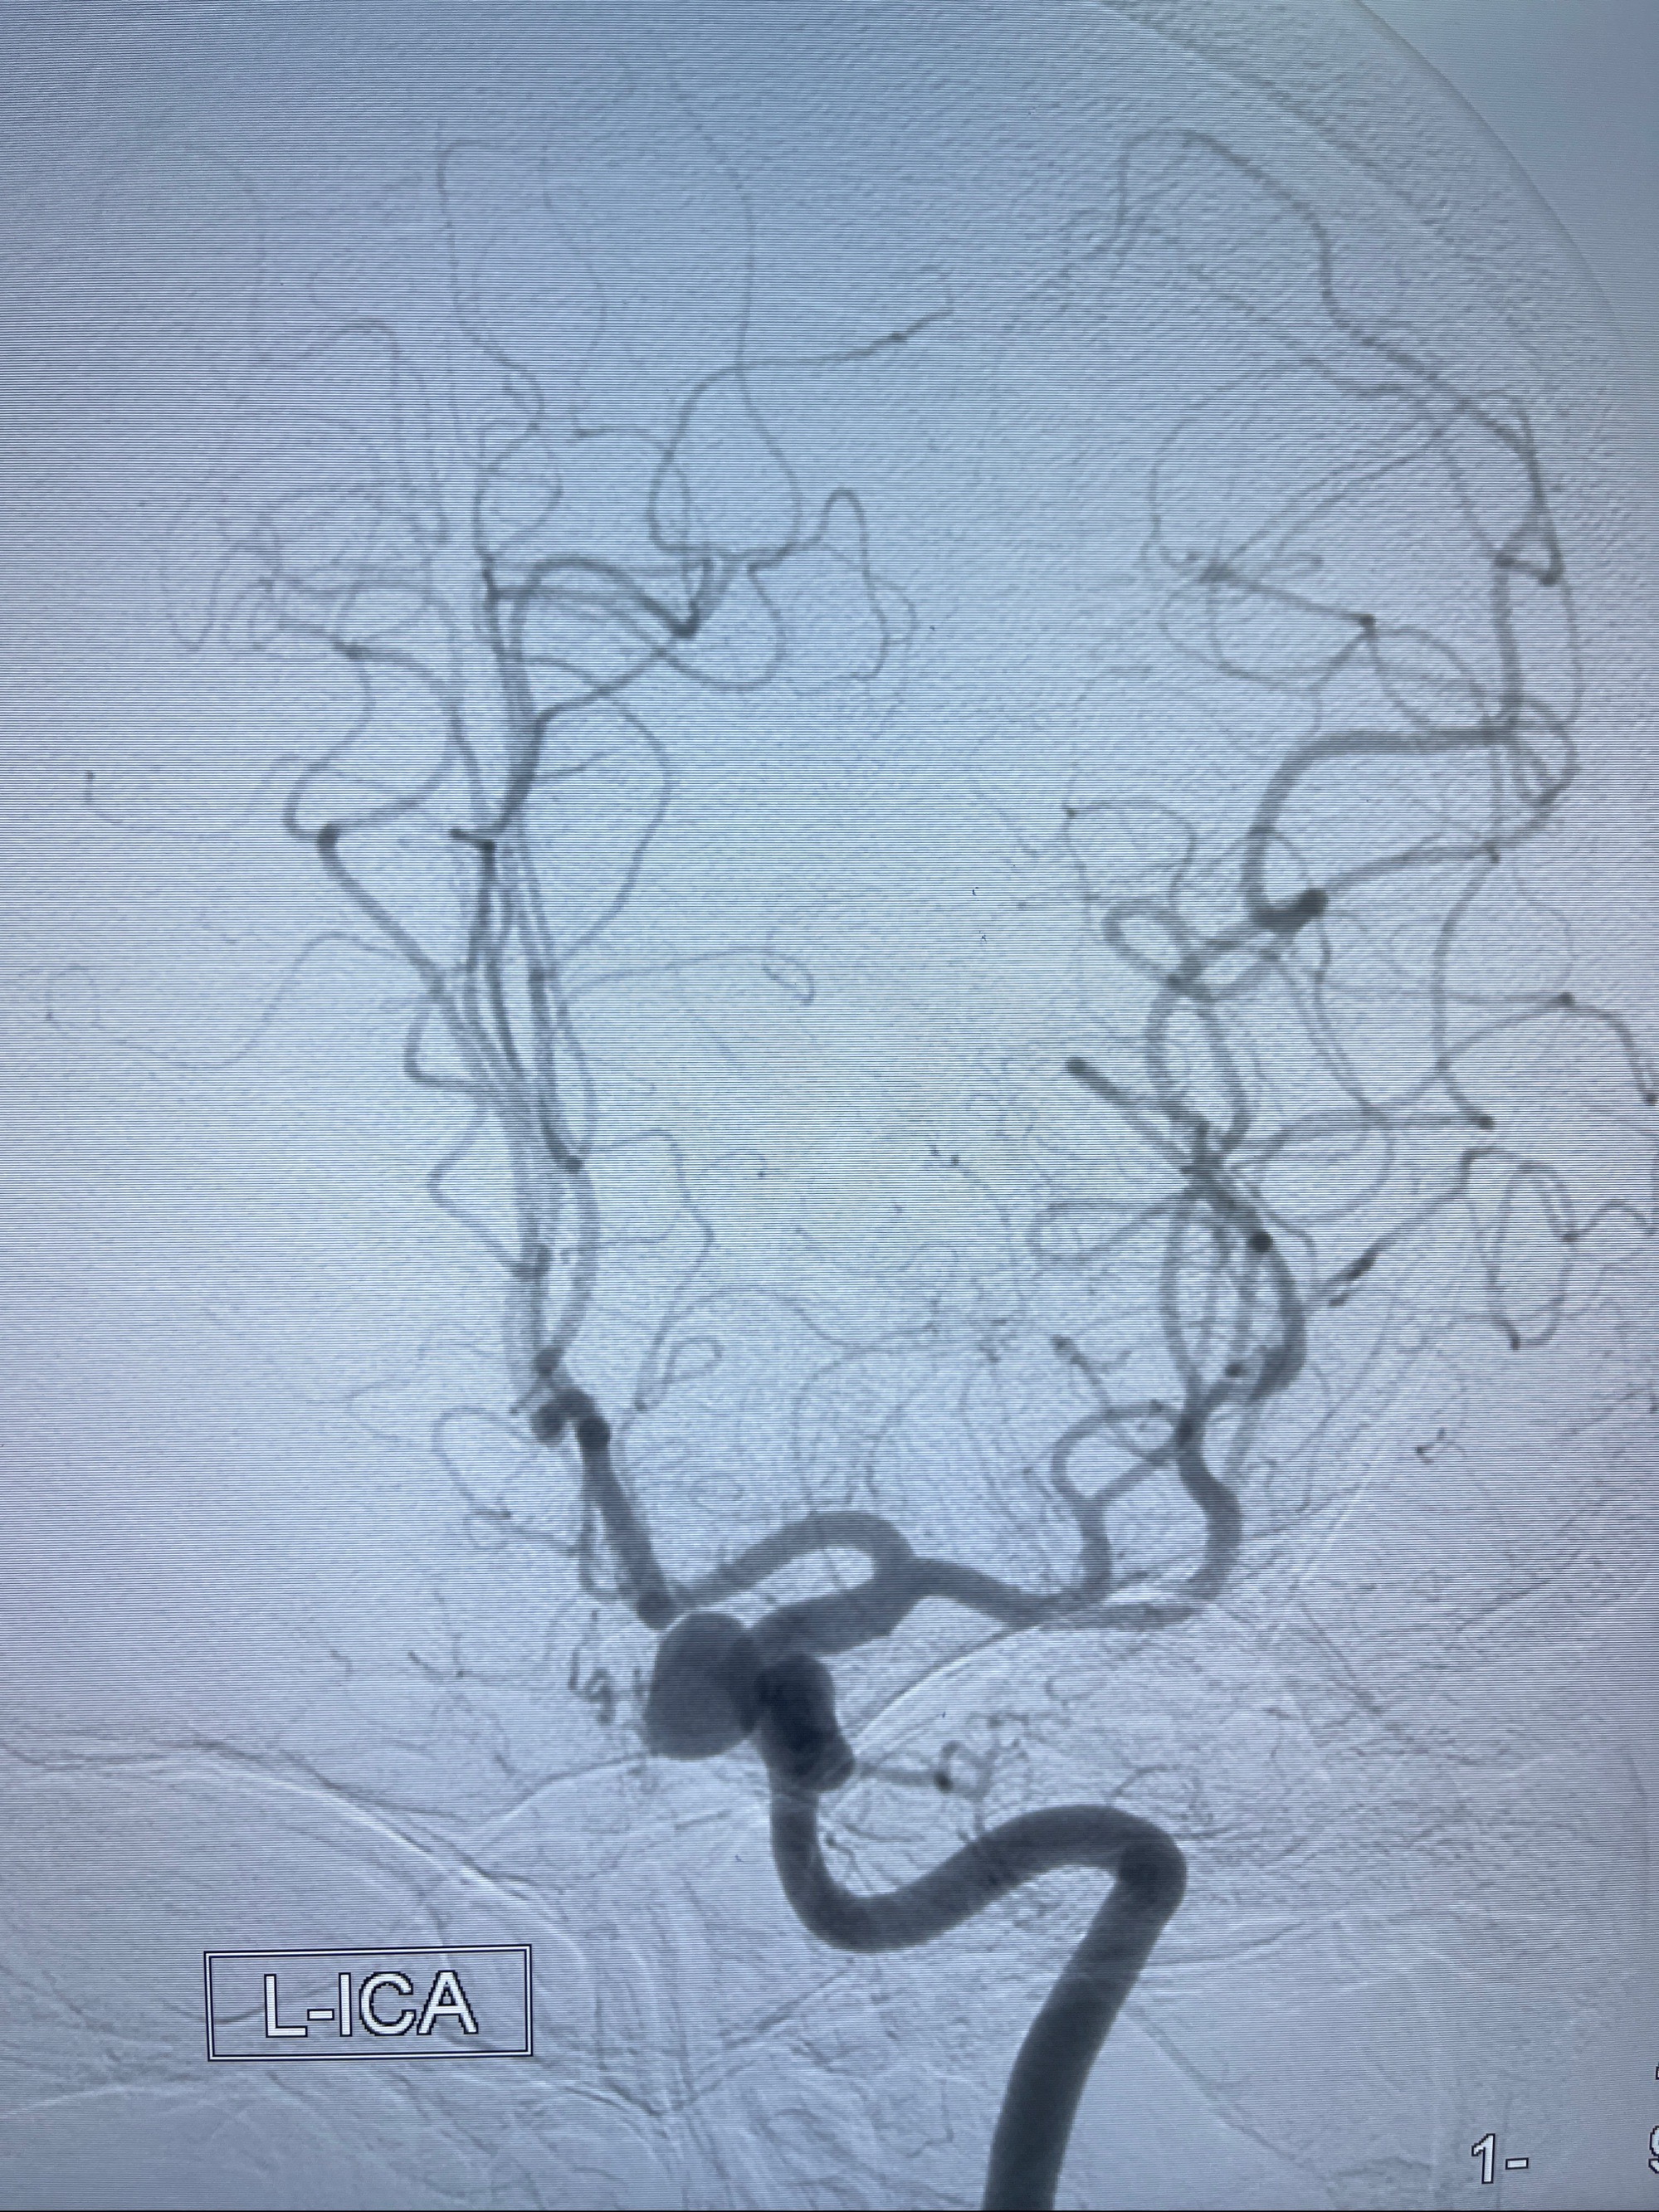

2023-08-30DSA:左侧颈内动脉眼动脉动脉瘤,约3*9.2*7.3mm大小

2023-09-06全麻下行左侧颈眼动脉瘤

密网支架辅助栓塞